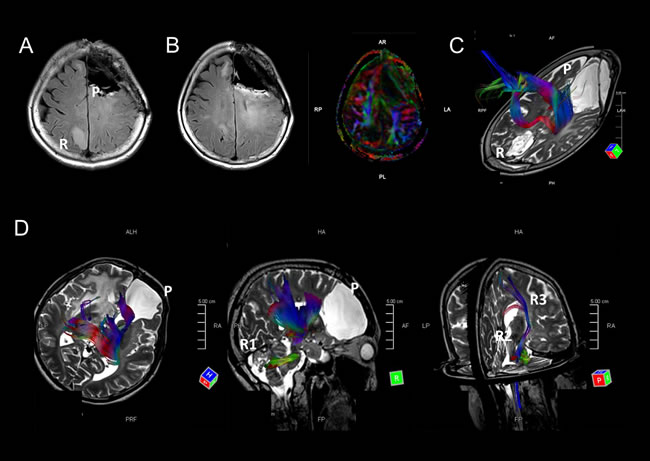

Figure 1: A. Five radiological recurrent patterns of gliomas: Type 1: local recurrence at the site of the primary lesion inside a single lobe; Type 2: diffuse enlargement from a primary lesion into different lobes; Type 3: an independent mass located in a different lobe, cerebellum, or brainstem that is continuous with the primary lesion in a T2/FLAIR high-intensity area; Type 4: a completely independent mass in a different lobe, cerebellum, or brain stem apart from the original lesion; and Type 5: intraventricular dissemination. B and C. A representative case of recurrent 1p/19q co-deleted glioma of Types 1 and 2 (W5). An MRI image (Gd-T1) taken 90 months after the first surgery (B); a recurrent contrast-enhanced tumor located around the cavity of the resected original tumor. At the time, the recurrent tumor was categorized as Type 1. MRI images (Gd-T1) after 115 months show a recurrent enlarged tumor located within the frontal and occipital lobes (C). D and E. A representative case of a TP53 mutant glioma of Type 3 (M14). A Gd-enhanced independent tumor was detected from a primary lesion (D). A FLAIR image reveals two lesions that are continuous with a high-intensity area (E). F-H. A representative case of a TP53 mutant glioma of Type 4 (M8). MRI images (FLAIR and Gd-T1) taken 61 months after the first surgery (F); an independent recurrent tumor, located in the right cerebellum, was detected apart from the primary tumor located in the right frontal lobe. An MRI image (Gd-T1) after 95 months shows that the recurrent tumor metastasized to the midbrain and cerebral peduncles (G). An MRI image (Gd-T1) after 100 months reveals that the recurrent tumors metastasized bilaterally to the basal nuclei (H). Abbreviation: Gd gadolinium.

Because IDH and TP53 mutant gliomas (astrocytomas in the revised WHO classification) showed remote intracranial recurrences, we retrospectively investigated the primary and recurrent sites of the tumors. Six of nine cases were from a frontal lobe to the other frontal lobe, and one case (M1) was initially located in a region in the frontal lobe and recurred in contralateral parietal lobe (Figure 2A and 2B). In another case (M8), the primary tumor was located in the right frontal lobe, and the tumor recurred in the ipsilateral cerebellum, metastasized to the midbrain, and subsequently found bilaterally in the basal nuclei (Figure 1F-1H). These findings led us to the hypothesis that remote intracranial recurrence in IDH and TP53 mutant gliomas may occur via major fiber bundles. Since the corpus callosum interconnects the bilateral frontal lobes, we analyzed whether major fiber bundles lay between the primary and recurrent tumor sites using diffusion tensor imaging (DTI) for distantly recurrent cases (M1 and M8). Fiber tracking images showed that the major fiber bundles did connect the primary and recurrent areas in these two cases (Figure 2C and 2D). In addition, comparing images generated by fluid-attenuated inversion recovery (FLAIR) and DTI in M1, high-intensity regions in FLAIR images were consistent with the area of the fiber bundles (Figure 2B). These results suggest that the recurrence of IDH and TP53 gliomas may occur via major fiber bundles.

Based on MRI, we classified tumor recurrence into the following five patterns: Type 1: local recurrence at the primary lesion inside a single lobe; Type 2: diffuse enlargement from the primary lesion to into a different lobe; Type 3: an independent mass located in a different lobe, cerebellum, or brainstem that is continuous with the primary lesion in a T2/ FLAIR high-intensity area; Type 4: a completely independent mass in a different lobe, cerebellum, or brain stem apart from the original lesion; and Type 5: intraventricular dissemination (Figure 1A). An independent mass was evaluated using the following sequences: T1-Gd, if it was contrast-enhanced; T2; and/or FLAIR. Intraventricular dissemination was radiologically defined if contrast-enhancement on MRI was detected in the ventricles. We defined Types 1 and 2 as a local type, and Types 3 and 4 as a remote type. Intraventricular dissemination can be complicated by the other types. Representative cases for Types 2, 3, and 4 are shown in Figure 1B and 1C, 1D and 1E, and 1F-1H, respectively.

We utilized DTI for surgical preparation in cases where tumors were located close to important long neural fibers. We analyzed DTI images using a fiber tracking method to examine correlations between tumor locations and major fiber bundles. We set up regions of interest (ROIs) between primary and recurrent lesions, allowing us to visualize the major fiber bundles within the ROIs.